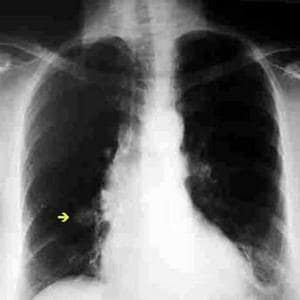

Una nueva herramienta de software podría ayudar a los médicos a eliminar los errores a la hora de evaluar cuando una mancha observada en un escáner de pulmón de un fumador es o no cancerosa, afirmaron investigadores este miércoles.

El método de evaluación del riesgo clínico descrito en la revista New England Journal of Medicine ayudó a determinar en 9 de cada 10 ocasiones si una mancha o lesión era benigna o maligna.

Los investigadores encontraron que los nódulos más grandes no significaban siempre cáncer, y que éstos se encontraban más a menudo en la parte alta del pulmón más que en los lóbulos inferiores.

El modelo de análisis del riesgo ayudó a determinar correctamente en el 94% de los casos si el nódulo fue o no canceroso, lo que los investigadores describieron como «excelente exactitud de predicción».

Además, ayudó a diagnosticar pequeños nódulos engañosos que tienen como máximo 10 milímetros de tamaño en un 90% de los casos.